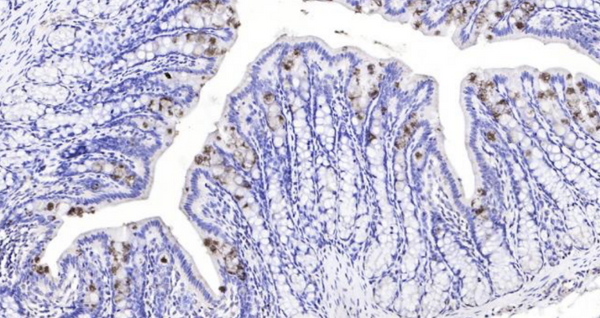

Rat TFF3 Ready-To-Use IHC Kit

Rat TFF3 Ready-To-Use IHC Kit

Cat. No.: IHC0103RSample Type: FFPE tissue

Trefoil peptides are protease resistant molecules secreted throughout the gut that play a role in mucosal healing. Trefoil peptides contain three intrachain disulfide bonds, forming the trefoil motif, or P-domain and clustered in human chromosome 21q22.3. Trefoil Factor 3 (TFF3) is one of three trefoil peptides secreted by epithelial cells that line mucus membranes in the large and small intestines and lower respiratory tract. TFF3 is mainly active as a disulfide-linked homodimer and may have a role in promoting cell migration in healing processes. It is involved in the maintenance and repair of the intestinal mucosa.

| 12 | Control slide (Rat small intestine) | 1 slide | RTU | RT |